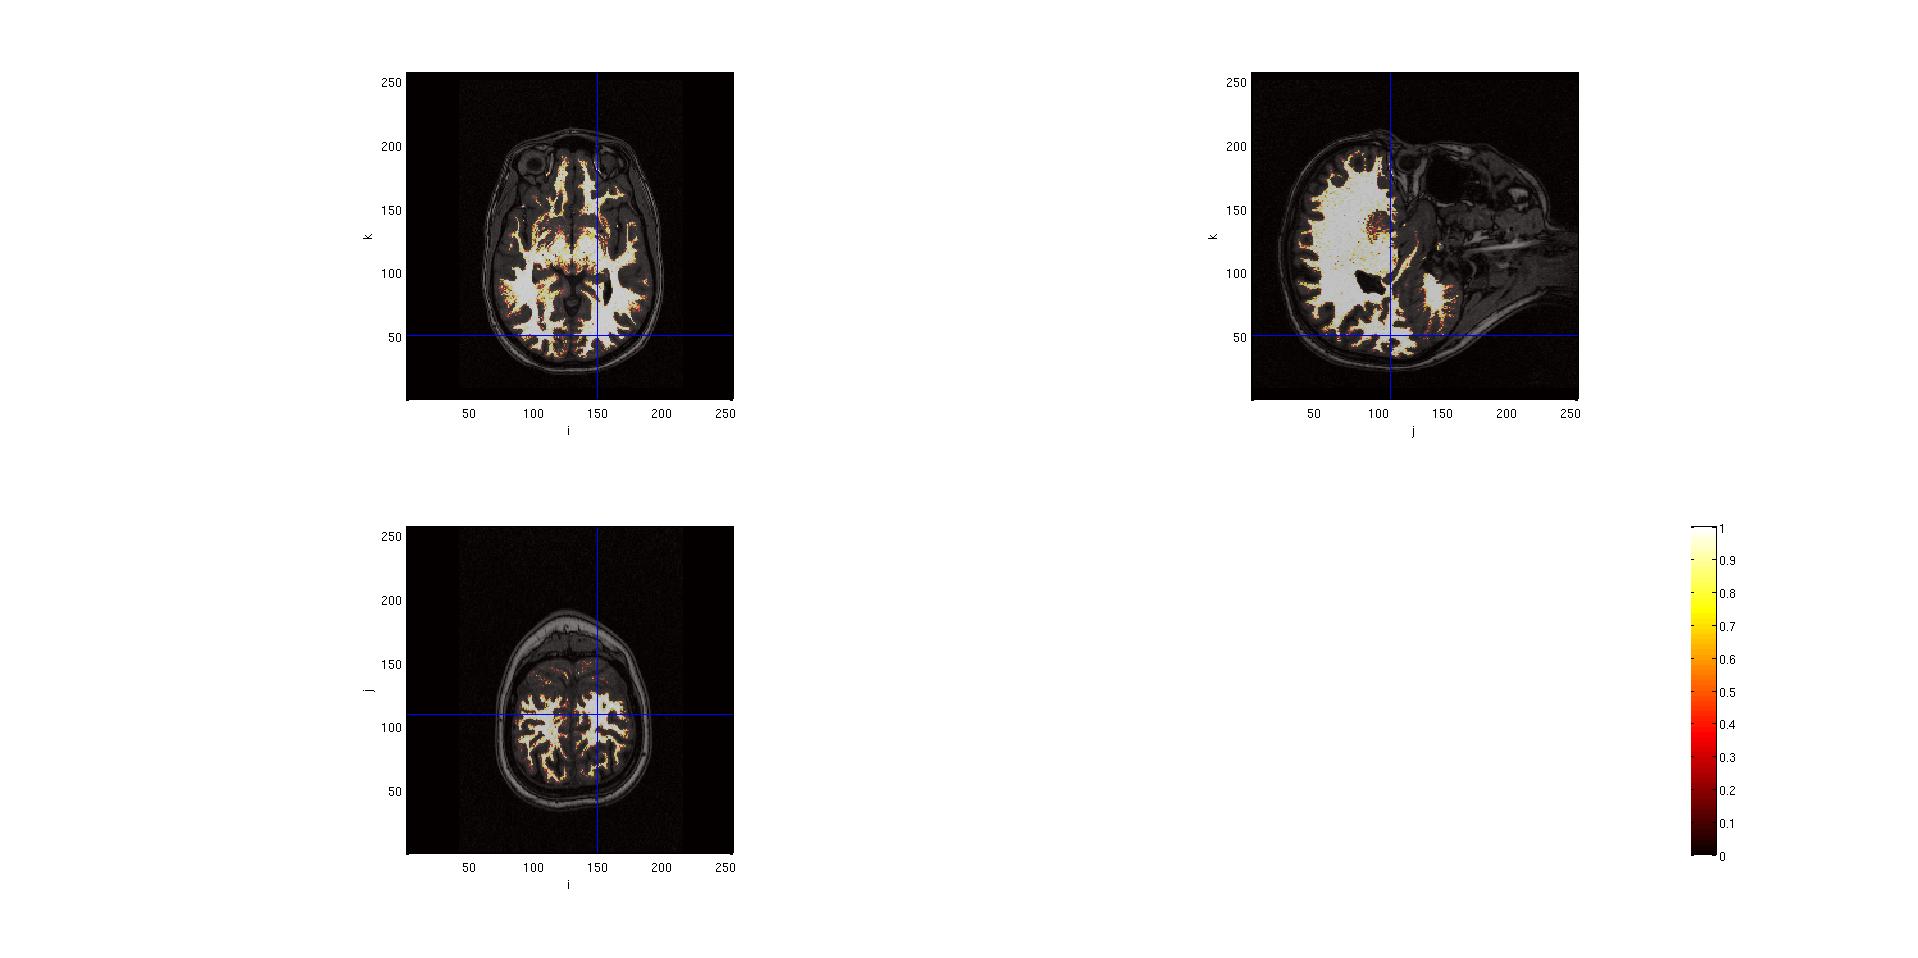

With this kind of segmentation, the output is the identification of the gray matter, the white matter and the cerebro-spinal fluid on the images. It is possible to look at the results of this segmentation.

seg.anatomy = mri.anatomy;

cfg = [];

cfg.funparameter = 'gray';

%or

%cfg.funparameter = 'white';

%cfg.funparamter = 'csf';

cfg.interactive = 'yes'; %(this allows to click on the images in order to see other slices

ft_sourceplot(cfg, seg);

Here are the outputs of ft_volumesegment on data from a .mgz volume, plotted with ft_sourceplot.

seg.white